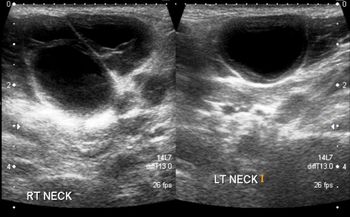

On palpation, the swelling was non-tender, soft, and mobile but did not feel fluid-filled. Here, view ultrasound findings and propose your diagnosis.